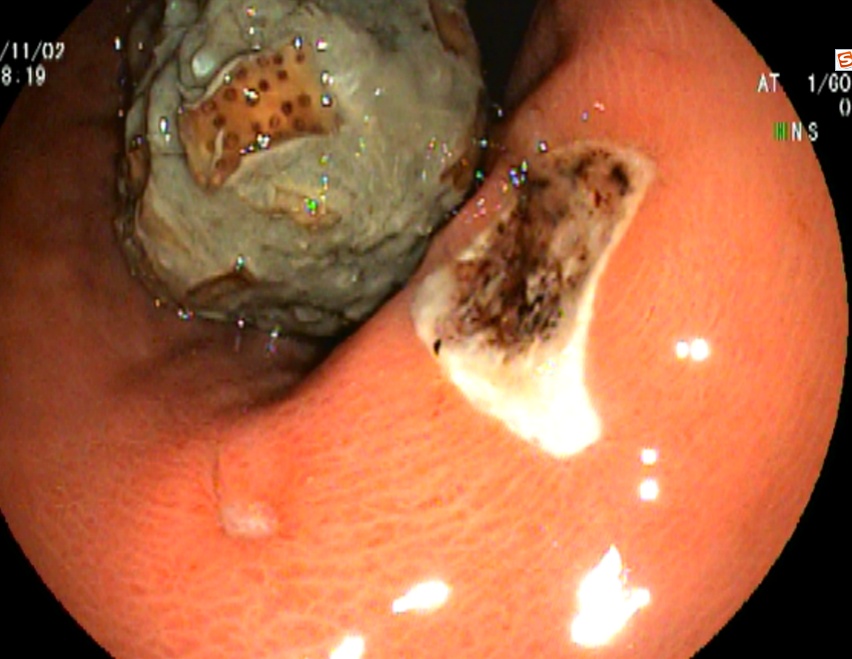

病房收治一名女性患者,68岁

患者主诉:阵发性上腹痛半月余

门诊行无痛胃镜,慢性浅表——萎缩性胃炎,胃石形成,建议内镜下治疗。

追问病史:平时喜食山楂,发病前进食柿饼。

B、内镜下碎石

①活检钳咬割、钳切、捣击、穿刺破坏胃石包膜或外壳,并反复用水冲洗。

②内镜下钢丝圈套器,套切石体,再用兜抓钳抓成碎块。

③内镜下微波碎石。

④在上述过程中,可经活检钳插入细塑管,对着被击碎的胃石注入10%碳酸氢钠150~200ml,有利于胃石的软化排出,提高治愈率。

治疗效果

兰索拉唑抑酸1周(30mg bid)和碳酸氢钠片口服1周(600mg tid),补液支持。

一周后镜下复查,胃石消除。